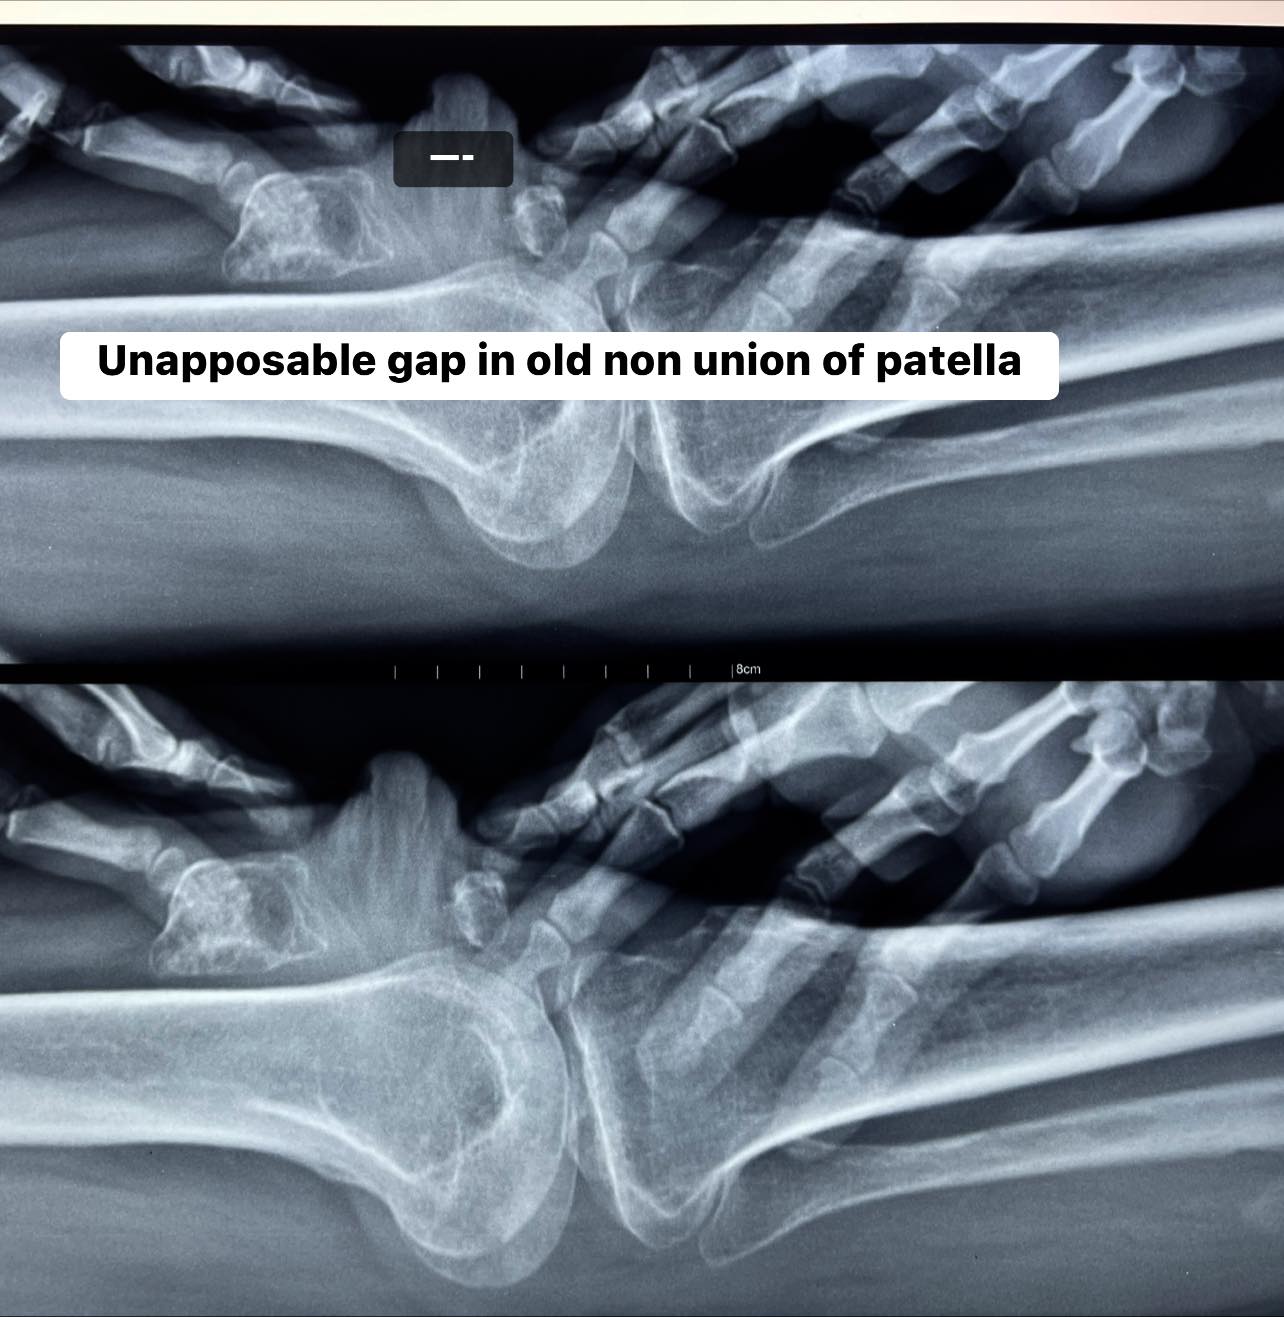

Quadriceps V-Y plasty is a useful tool sometimes needed in extremely bad knees needing total knee replacement or in this case a 6-month-old non union of patella where the two fractured ends are not coming together dude to quadriceps contracture.